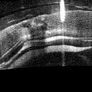

Retinoschisis

A 14-year-old male patient was admitted for visual assessment. Visual acuity s/c in the right eye and 20/80 in the left eye. According to family members, he reported low vision since childhood. He had already undergone photocoagulation treatment at another service for which he had a diagnostic hypothesis of Coats' disease. Laboratory tests were requested (HIV, TOXO, TOXOCARIASIS, ACE, VDRL, PPD). In the evaluation, there was significant exudation in the posterior pole, some vascular irregularities in the right eye. In the left eye, there is retinoschisis affecting the entire posterior pole and the nasal region to the optic disc, macula with a characteristic chariot-wheel appearance, well exemplified by OCT-A (Structrure Deep: IPL - 25, OPL - 25).

Photographer: JEFFERSON R SOUSA - Study Center and Ophthalmological Research Dr. Andre M V Gomes, Institute Dr. Suel Abujamra São Paulo-Brazil

Imaging device: Optical coherence tomography system Optical Coherence Tomography system OCT CIRRUS 5000, Line Protocol, HD 21 line. Cirrus 5000 does not do a wide-angle tomographic image. (Structrure Deep: IPL - 25, OPL - 25).

Condition/keywords: Coats' disease, retinoschisis